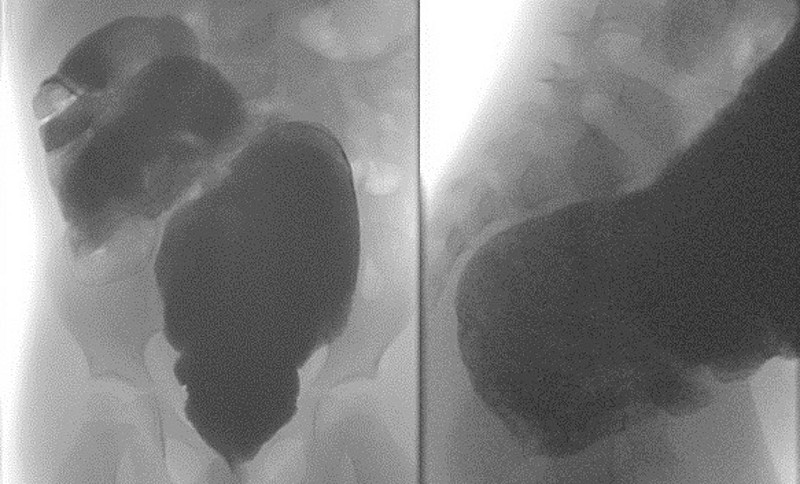

Der erste Schritt zur Diagnose ist ein ausführliches Anamnesegespräch, bei dem typische Symptome wie feste Stuhlballen, Schmerzen bei der Defäkation, Stuhlgang nur durch abführende Maßnahmen oder tagelang ausbleibender Stuhlgang erfragt werden. Es folgt eine körperliche Untersuchung, bei der Anzeichen wie ein geblähtes, schmerzhaftes Abdomen, tastbare feste Stuhlwalzen und erweiterte Dickdarmschlingen festgestellt werden können. Im Ultraschall lassen sich diese stuhlgefüllten, erweiterten Darmschlingen, einschließlich des Mastdarms, ebenfalls gut darstellen. Wenn die Ergebnisse dieser Untersuchungen auf Morbus Hirschsprung hindeuten, sollte eine Röntgenuntersuchung des Dickdarms mit Kontrastmittel (Kolon-Kontrasteinlauf) durchgeführt werden (Abbildung 1). Die endgültige Diagnose kann jedoch nur durch eine Rektumbiopsie gesichert werden.

Abbildung 1: Kolon-Kontrasteinlauf bei einem 3,5-jährigen Patienten mit Megakolon bei Morbus Hirschsprung.